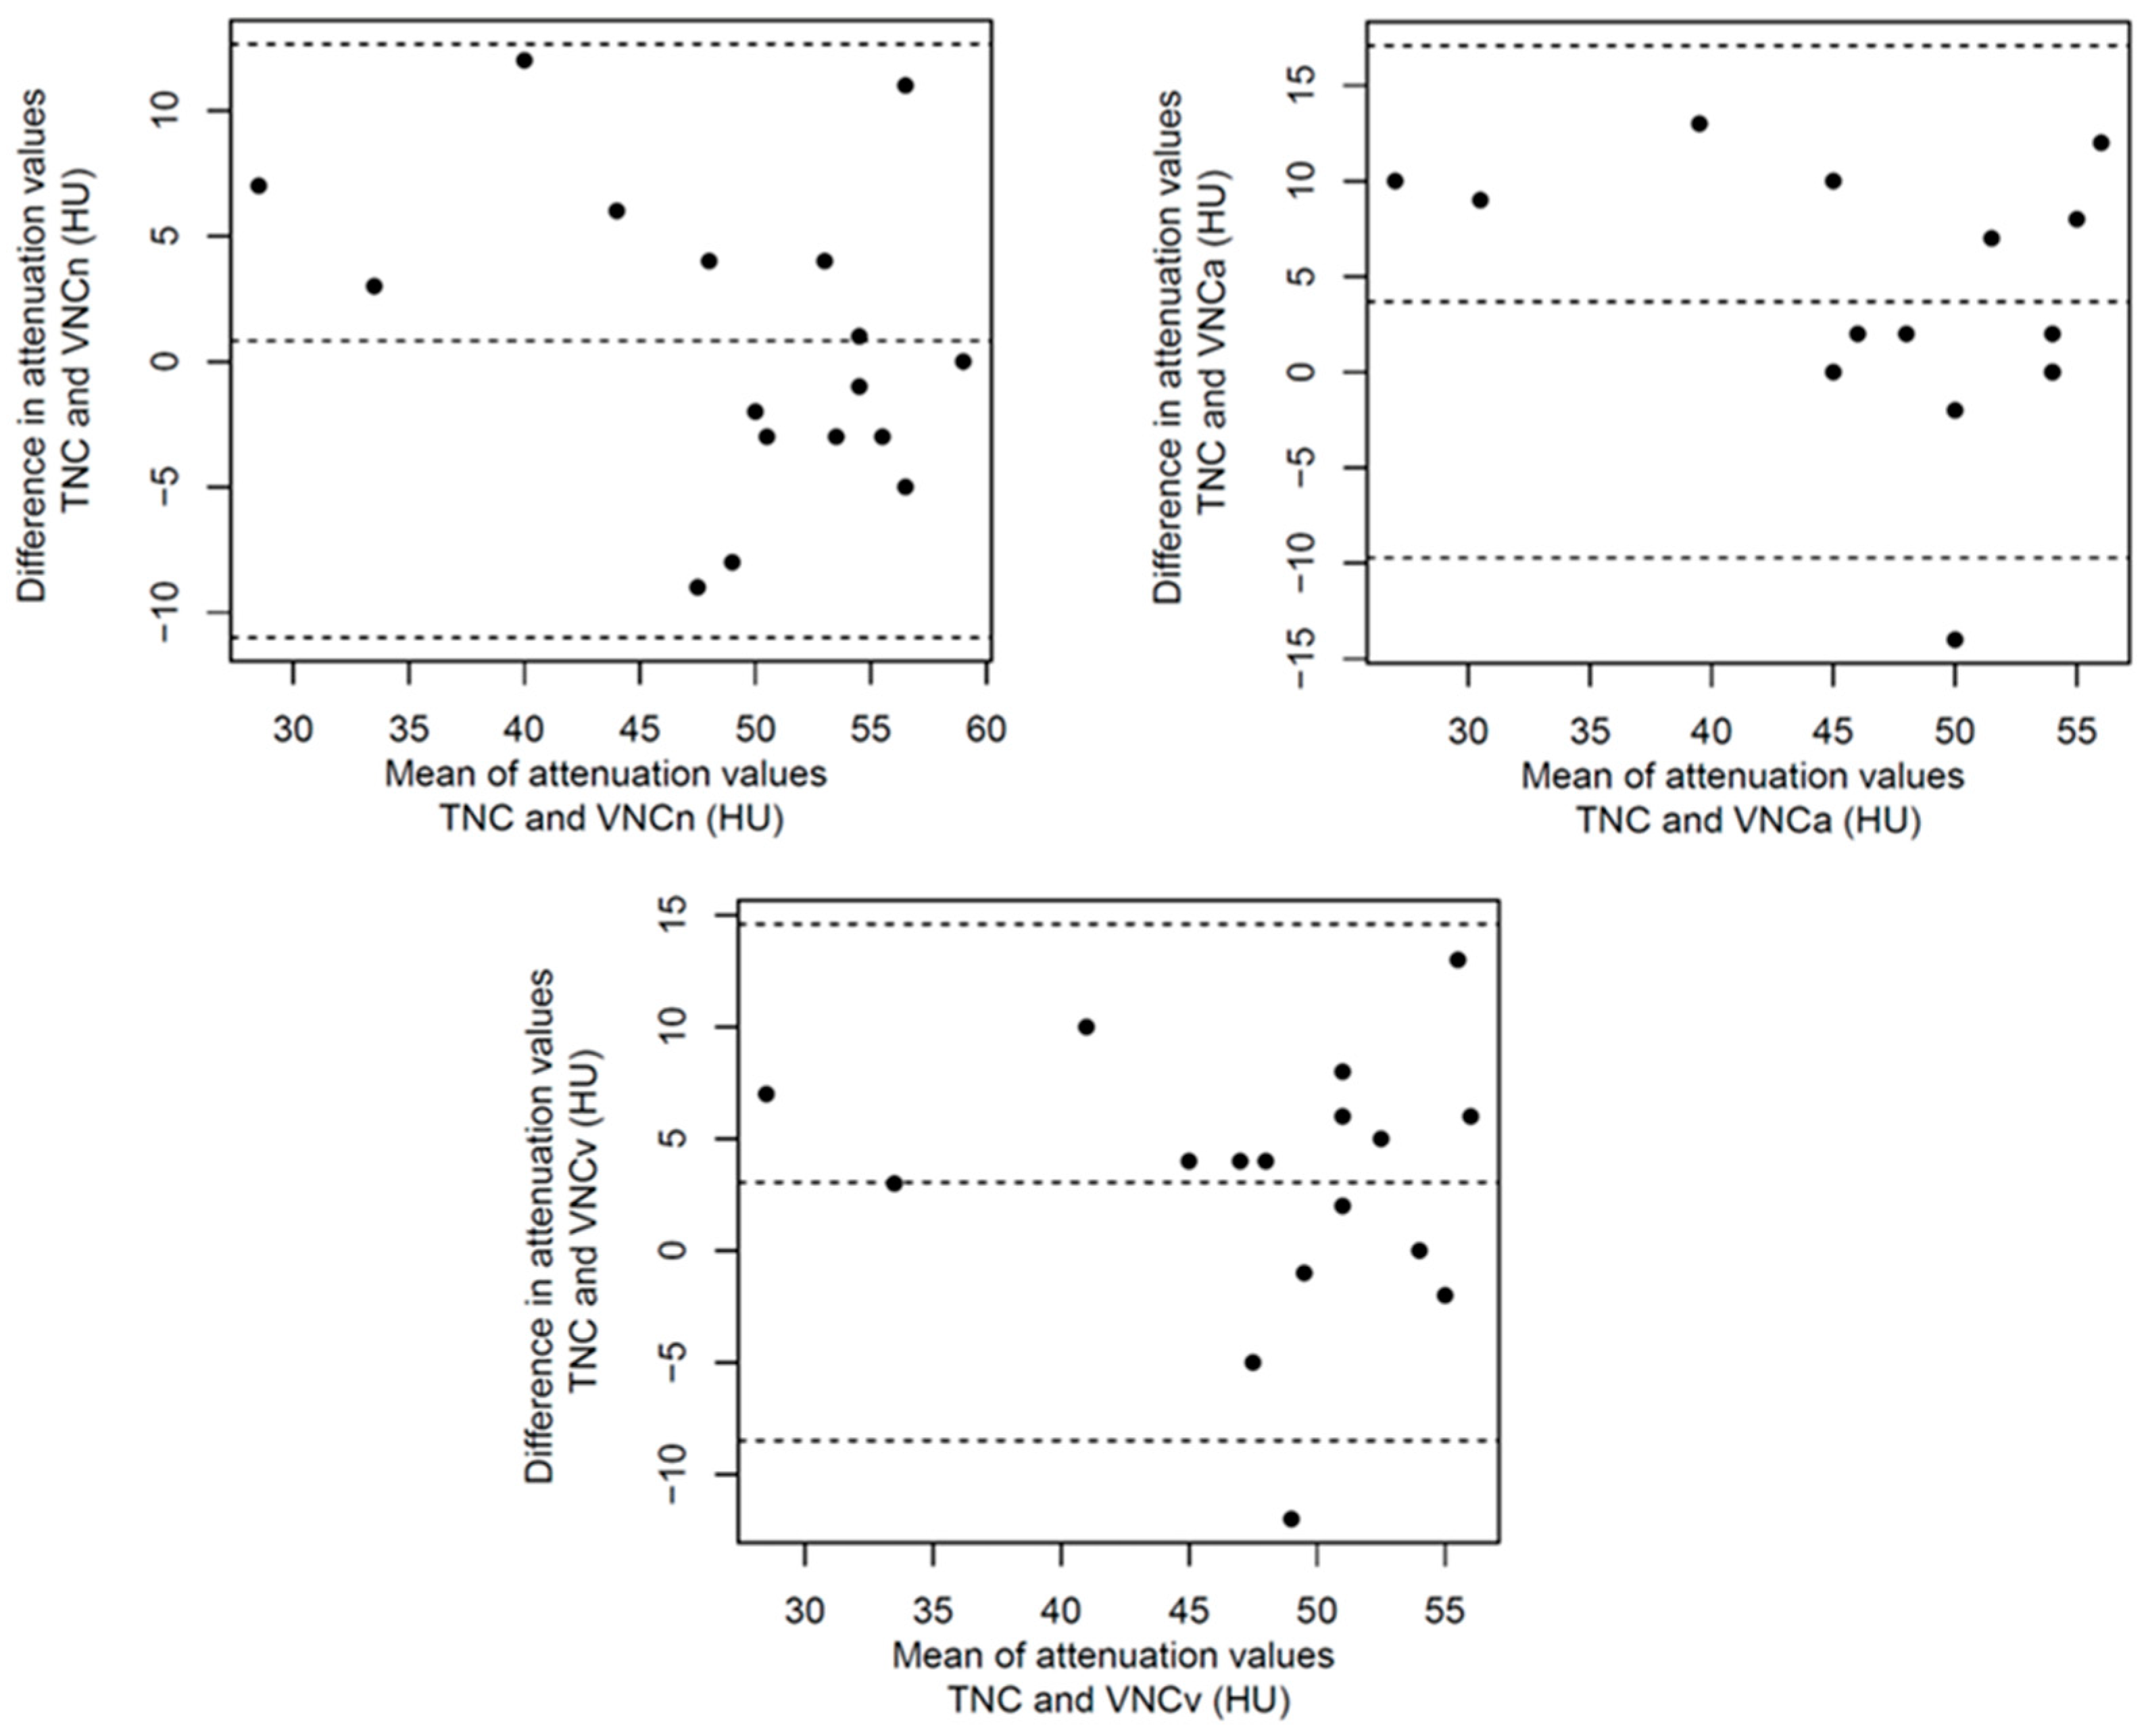

3.2. Structured Measurement